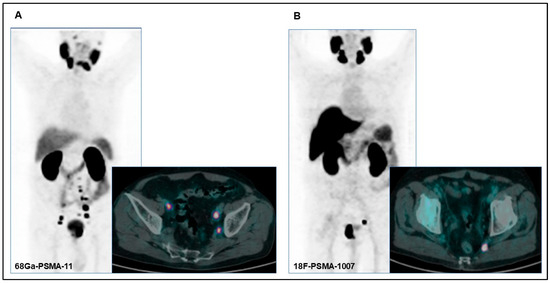

An Evaluation of the Diagnostic Accuracy of [68Ga]Ga-PSMA-11 vs. [18F]F-PSMA-1007 PET/CT for Lymph Node Staging in Patient Candidates for Radical Prostatectomy and Lymph Node Dissection: A Single Institutional Analysis

3.2. Nodal Staging Assessment

3.3. PSMA PET/CT Diagnostic Performance